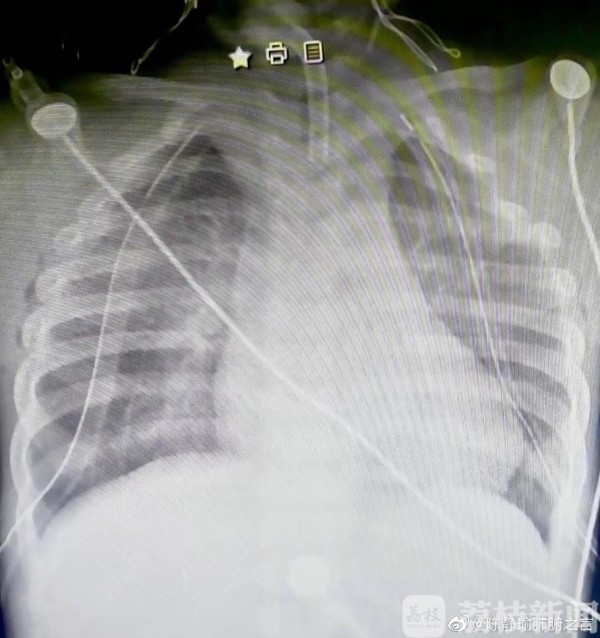

清晨六点,团队在广州获取供肺后,马不停蹄,于10:40赶到无锡市人民医院。陈静瑜教授第一次用了2.5倍放大镜切除二侧病肺,完成6个吻合口,至13:50双肺吻合完成 ,4个小时内完成了这例2岁孩子的双肺移植手术,术后2小时胸片清晰、氧合指数良好,孩子二氧化碳分压已降到67。目前,孩子已经清醒。